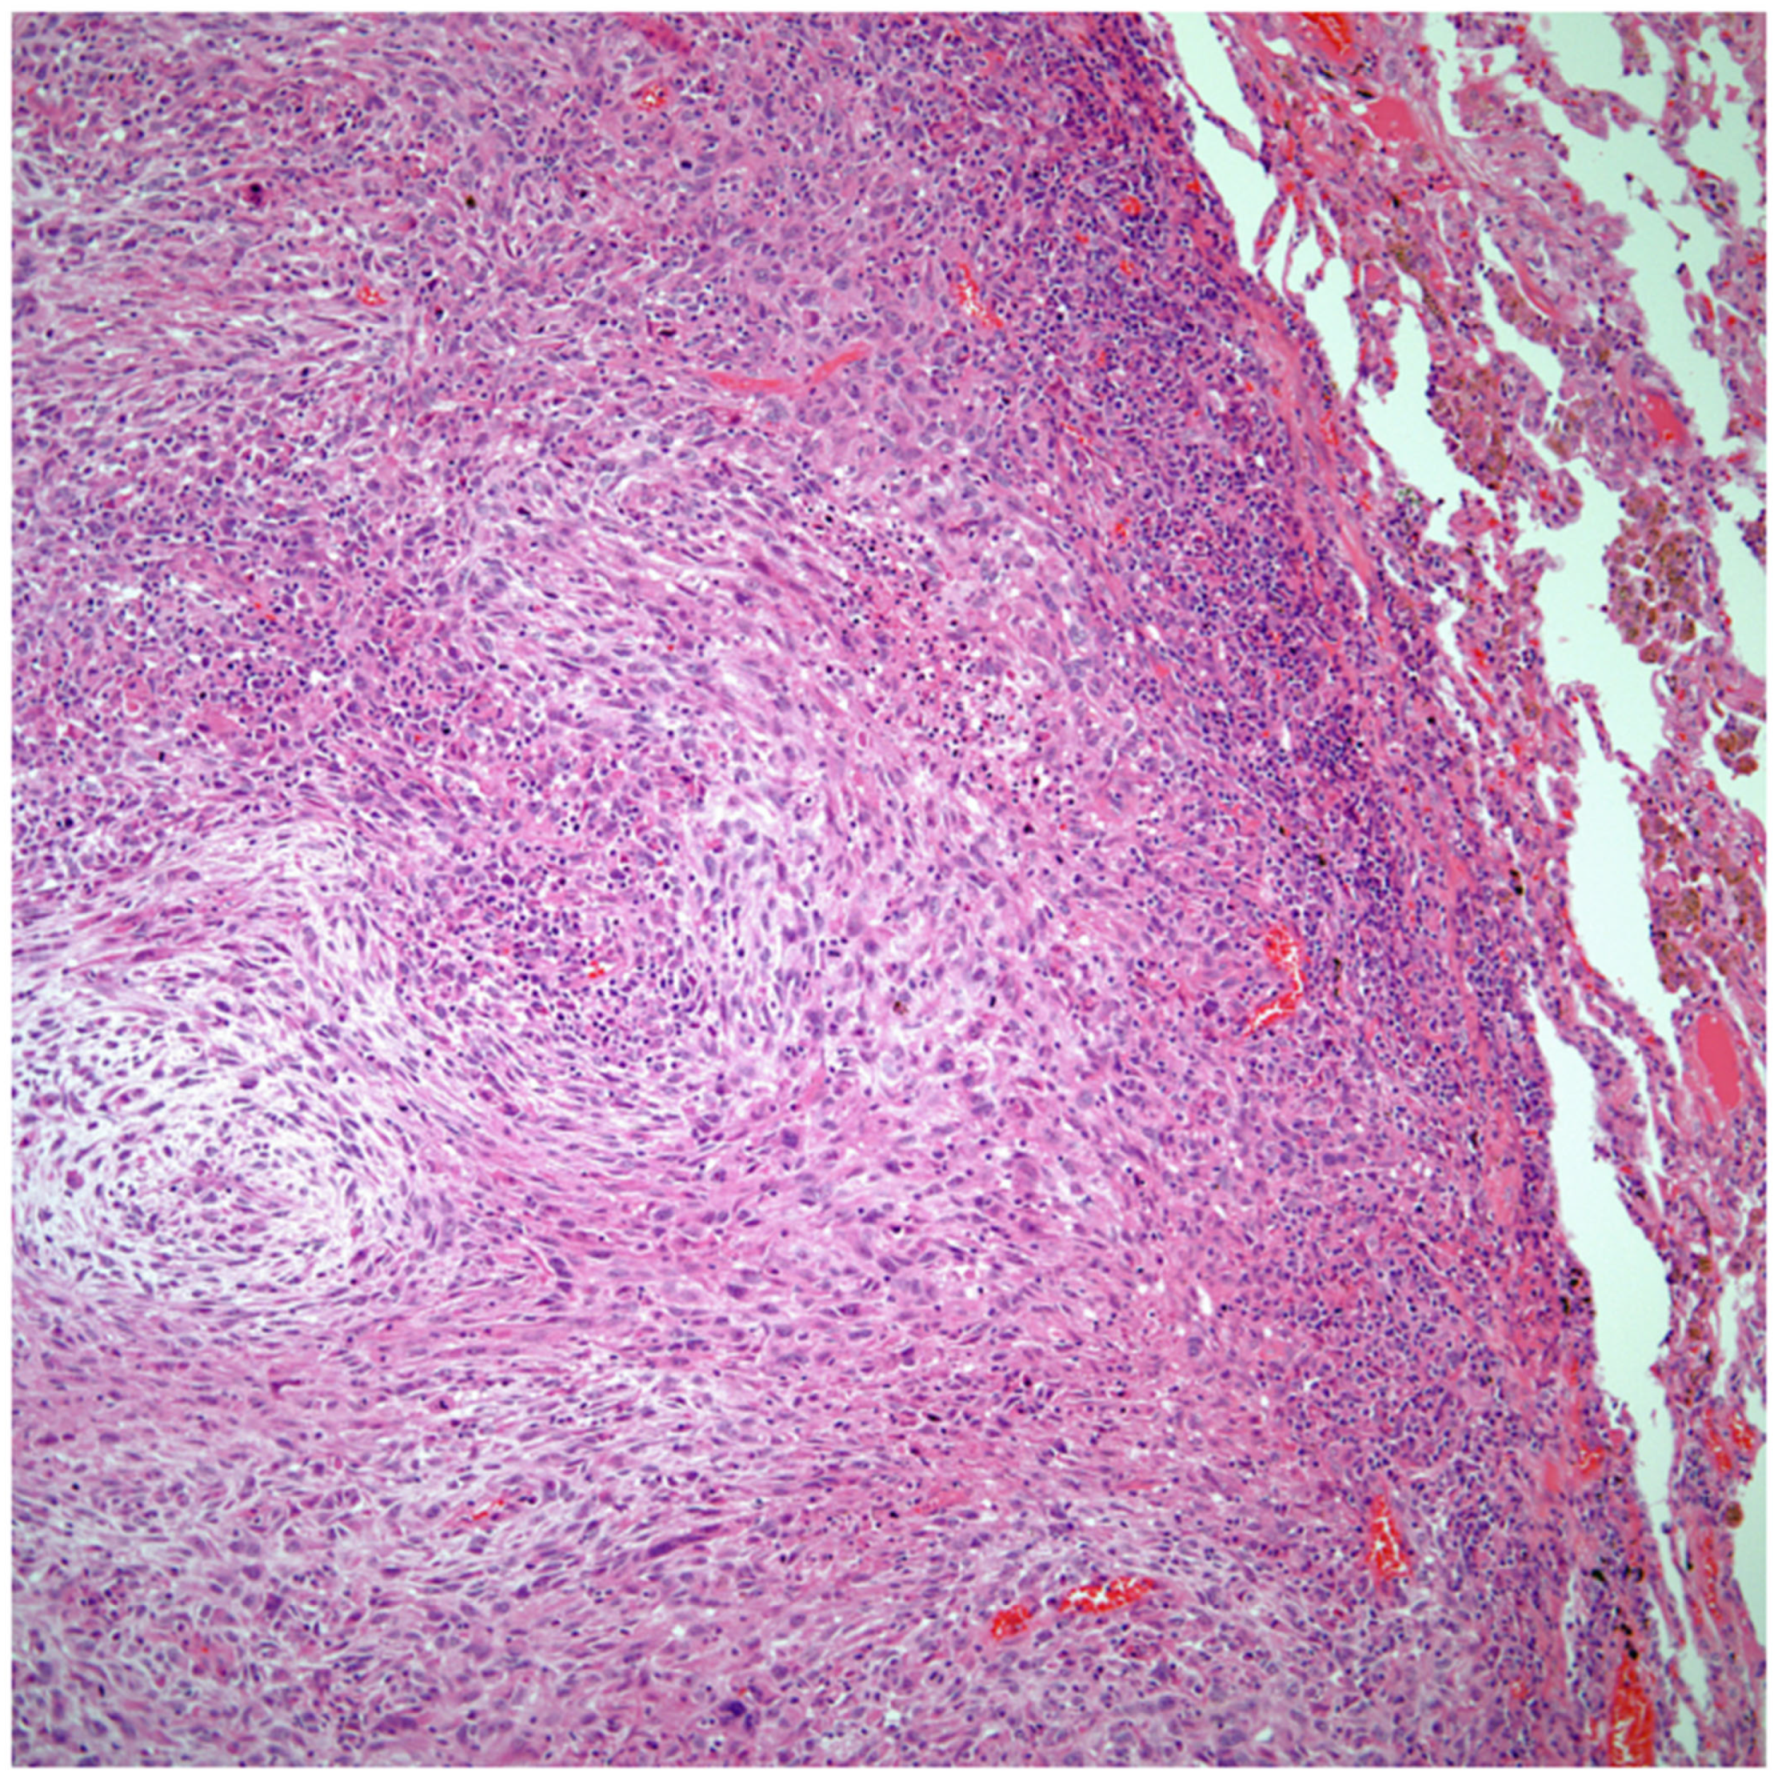

Sarcomatoid carcinomas: These tumors show a tightly packed spindle cell proliferation composed of slender cells with fusiform nuclei and inconspicuous nucleoli, replacing normal lung parenchyma. The tumors are well delimited but not encapsulated (Figure 1). Cellular atypia is variable and may show areas of mild to moderate to marked atypia. Mitotic figures also vary and may be inconspicuous or may be evident with the presence of atypical mitotic figures (Figure 2A,B). In high-grade tumors, the presence of necrosis and hemorrhage is prominent and is mixed with the neoplastic component. Important to recognize is that sarcomatoid carcinomas may be associated with areas of otherwise conventional non-small cell carcinoma such as adenocarcinoma or squamous cell carcinoma (Figure 3A,B). In addition, sarcomatoid carcinoma may also show the presence of bizarre giant cells admixed with the spindle cell component (pleomorphic carcinoma) (Figure 4).

Figure 1.

Sarcomatoid carcinoma of the lung showing a well circumscribed tumor replacing lung parenchyma.